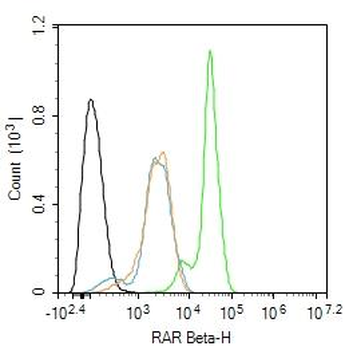

RARB Rabbit Polyclonal Antibody [orb11327]

FC, ICC, IF, IHC-Fr, IHC-P, WB

Bovine, Canine, Gallus, Porcine, Rat

Human, Mouse

Rabbit

Polyclonal

Unconjugated

50 μl, 100 μl, 200 μlTIG2 Rabbit Polyclonal Antibody [orb11481]